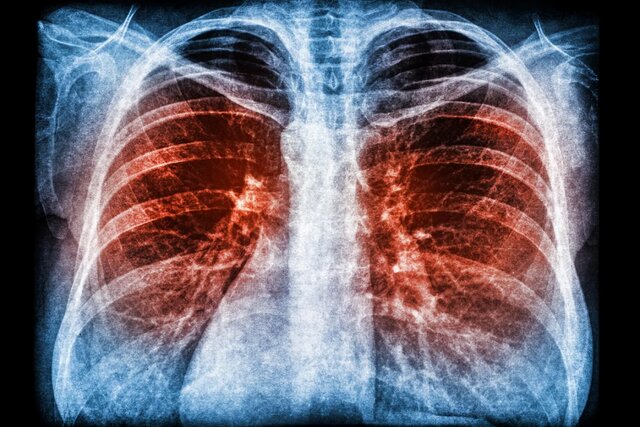

یک مطالعه بینالمللی به رهبری دانشمندان سنگاپوری نشان میدهد باکتریهایی که تصور میکردیم بی خطر هستند میتوانند باعث وخامت بیماریهای ریوی موجود شوند.

به گزارش ایسنا و به نقل از استیدی، گروهی از دانشمندان بینالمللی کشف کردهاند که نایسریا(Neisseria) که سردهای از باکتریهای ساکن در بدن انسان است، آنطور که پیش از این تصور میشد بیضرر نیست. در واقع، این باکتریها میتوانند باعث عفونت در بیماران مبتلا به برونشکتازی، آسم و بیماری انسداد مزمن ریه(COPD) شوند.

در یک مطالعه قابل توجه، که در تاریخ ۱۴ سپتامبر ۲۰۲۲ در مجله "Cell Host & Microbe" منتشر شد، محققان شواهدی قطعی ارائه کردند که نشان میداد گونههای نایسریا میتوانند باعث وخامت بیماریهای ریوی شوند. دانشمندان به رهبری دانشگاه فناوری نانیانگ، سنگاپور(NTU) به انجام این تحقیقات پرداختند.

برونشکتازی یک بیماری مزمن است که در آن راههای هوایی ریهها به دلایل نامعلومی به طور غیر طبیعی بزرگ میشود. این بیماری در میان آسیاییها تا چهار برابر بیشتر از همتایان غربیشان شایع است و همچنین میتواند پس از بهبودی از سل رخ دهد.